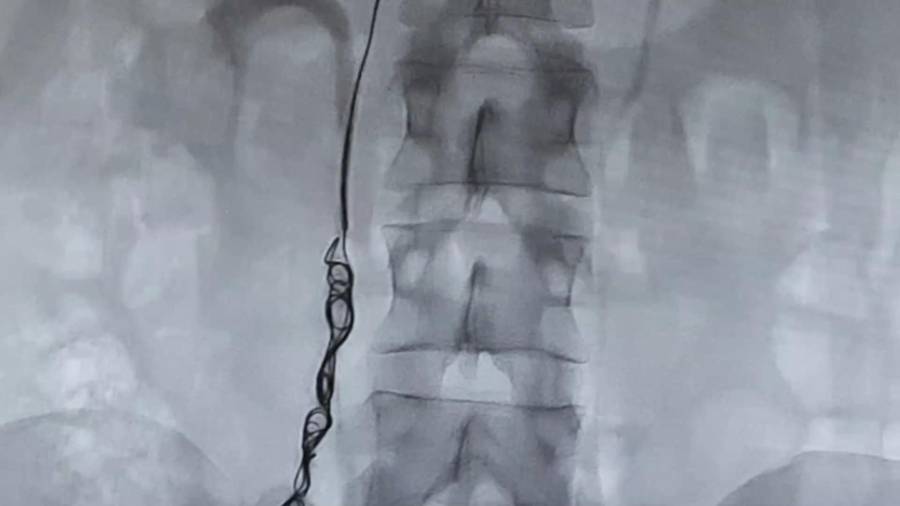

- Arteriography

A minimally invasive diagnostic technique providing anatomical and dynamic information about arteries. It allows immediate treatment with angioplasty when necessary.

Our treatment approach focuses on embolizing all pathological pelvic veins, significantly improving patients’ quality of life. Our Angiology and Vascular Surgery service collaborates closely with the Postpartum Unit to support patients experiencing PCS symptoms after childbirth.

We employ techniques like radiofrequency for varicose veins in the lower limbs, pelvic varices embolization, venous stenting for compressions, and pharmacomechanical thrombolysis for venous thrombosis. These procedures effectively improve venous health and quality of life.